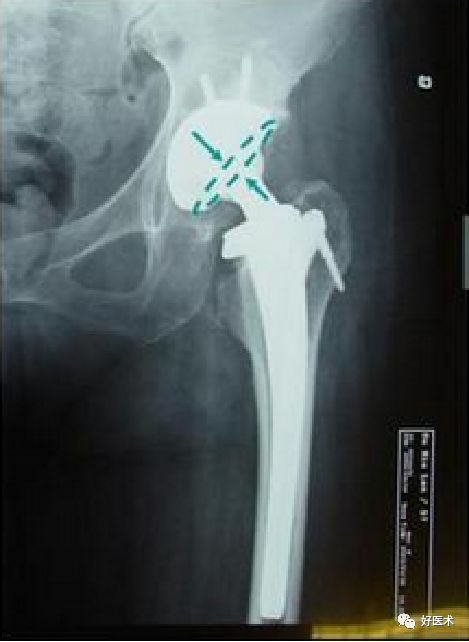

柄-髓腔比

-

分别在正位和侧位X 线片上, 在三个水平( 小转子上缘、柄的中部、柄尖端近侧1 cm) 检测假体宽度与髓腔宽度之比(B/A×100%) 来确定。

正位片上>80%, 侧位片>70%为匹配满意。